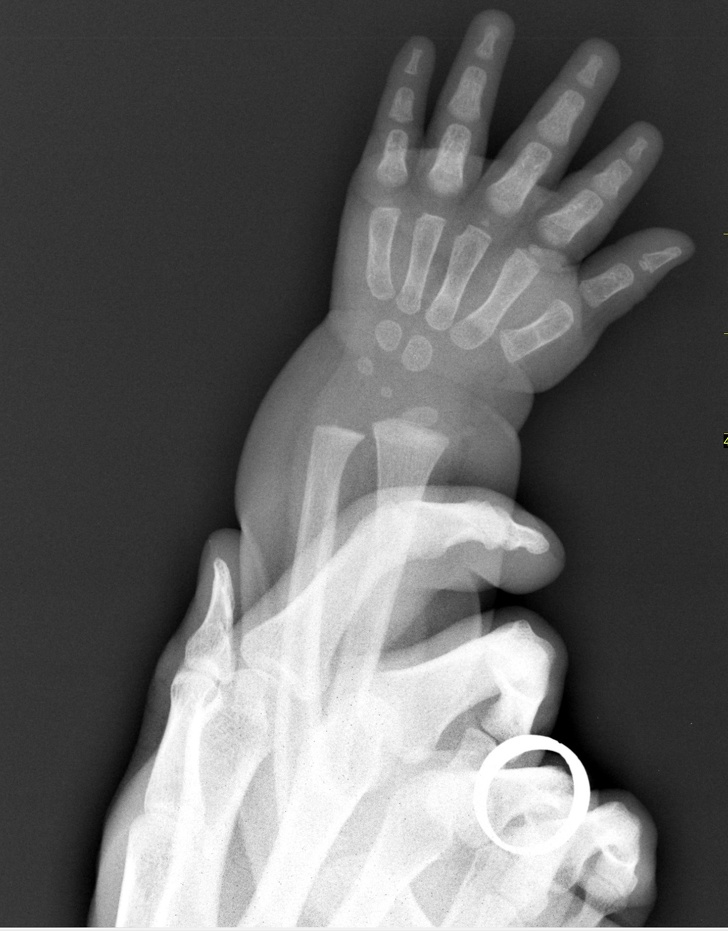

6. Рентгенівський знімок руки дитини, яка відрізняється від руки дорослого тим, що на місці деяких кісток до певного віку розташовані хрящі

9. Рентгенівський знімок руки дорослої людини і дитини